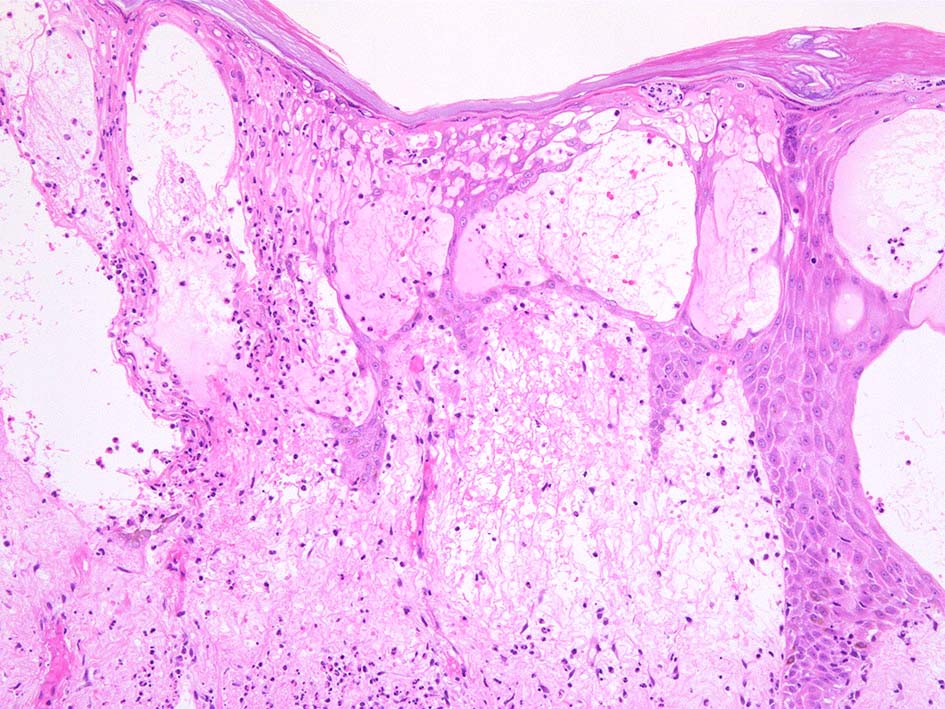

真皮上層浮腫がつよくなり表皮下水疱を形成することがある. 水疱内にはフィブリンや炎症細胞が多数認められる.

表皮基底層の液状変性, また液状変性ほど強くなくともvesicleの形成が見られることがある.

HE x40. 表皮下水疱あり. 真皮上層は浮腫状. 真皮から皮下組織にかけて, 多数の好中球が浸潤している. リンパ球, 好酸球が混在, 核破砕物を貪食するマクロファージが増加. 膠原線維にはところどころ変性が見られる.

真皮上層には核破砕物が多く, 好中球浸潤が認められる. 慢性炎症性細胞も浸潤している.